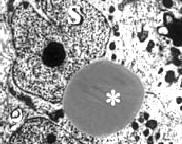

De testes produceren zaadcellen in de seminiferous tubules. Daar vind je de cellen van Sertoli (s) die de cellen voeden waaruit de spermacellen ontstaan (g). Hiernaast zie je hoe dat er bij gezonde dieren uitziet.

In de voedende Sertolicellen waren bij de dieren die clnebuterol hadden gekregen bovendien vetdruppeltjes verschenen. Zo'n druppel is hiernaast met een * aangegeven.